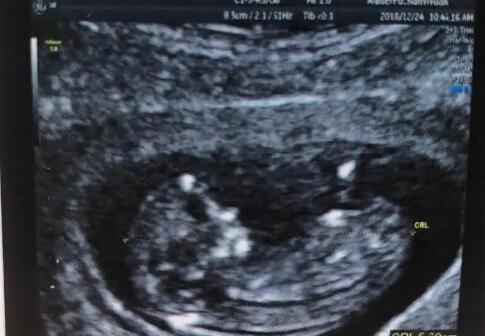

今天去產檢,一切正常。懷孕期間沒吃什么保養品,就吃了葉酸,中途買了一罐孕婦奶粉到現在還有一半。

水果吃了不少,平常也沒什么忌口的。

懷孕前57kg ,現在體重59kg 因為體重沒怎么漲,肚子也不是很明顯。擔心寶寶的營養跟不上,醫生說不用看肚子大小,B超顯示寶寶現在體重550g 而且吸收的很好,我就放心了

我今天看到寶寶的小JJ啦,醫生也說是個小王子。

醫生說一個月后再來產檢一次,可是也沒交代要做四維或者糖篩之類的哎~搞不懂